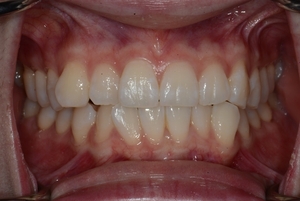

ガタガタとした歯並びや八重歯(叢生)CASE69